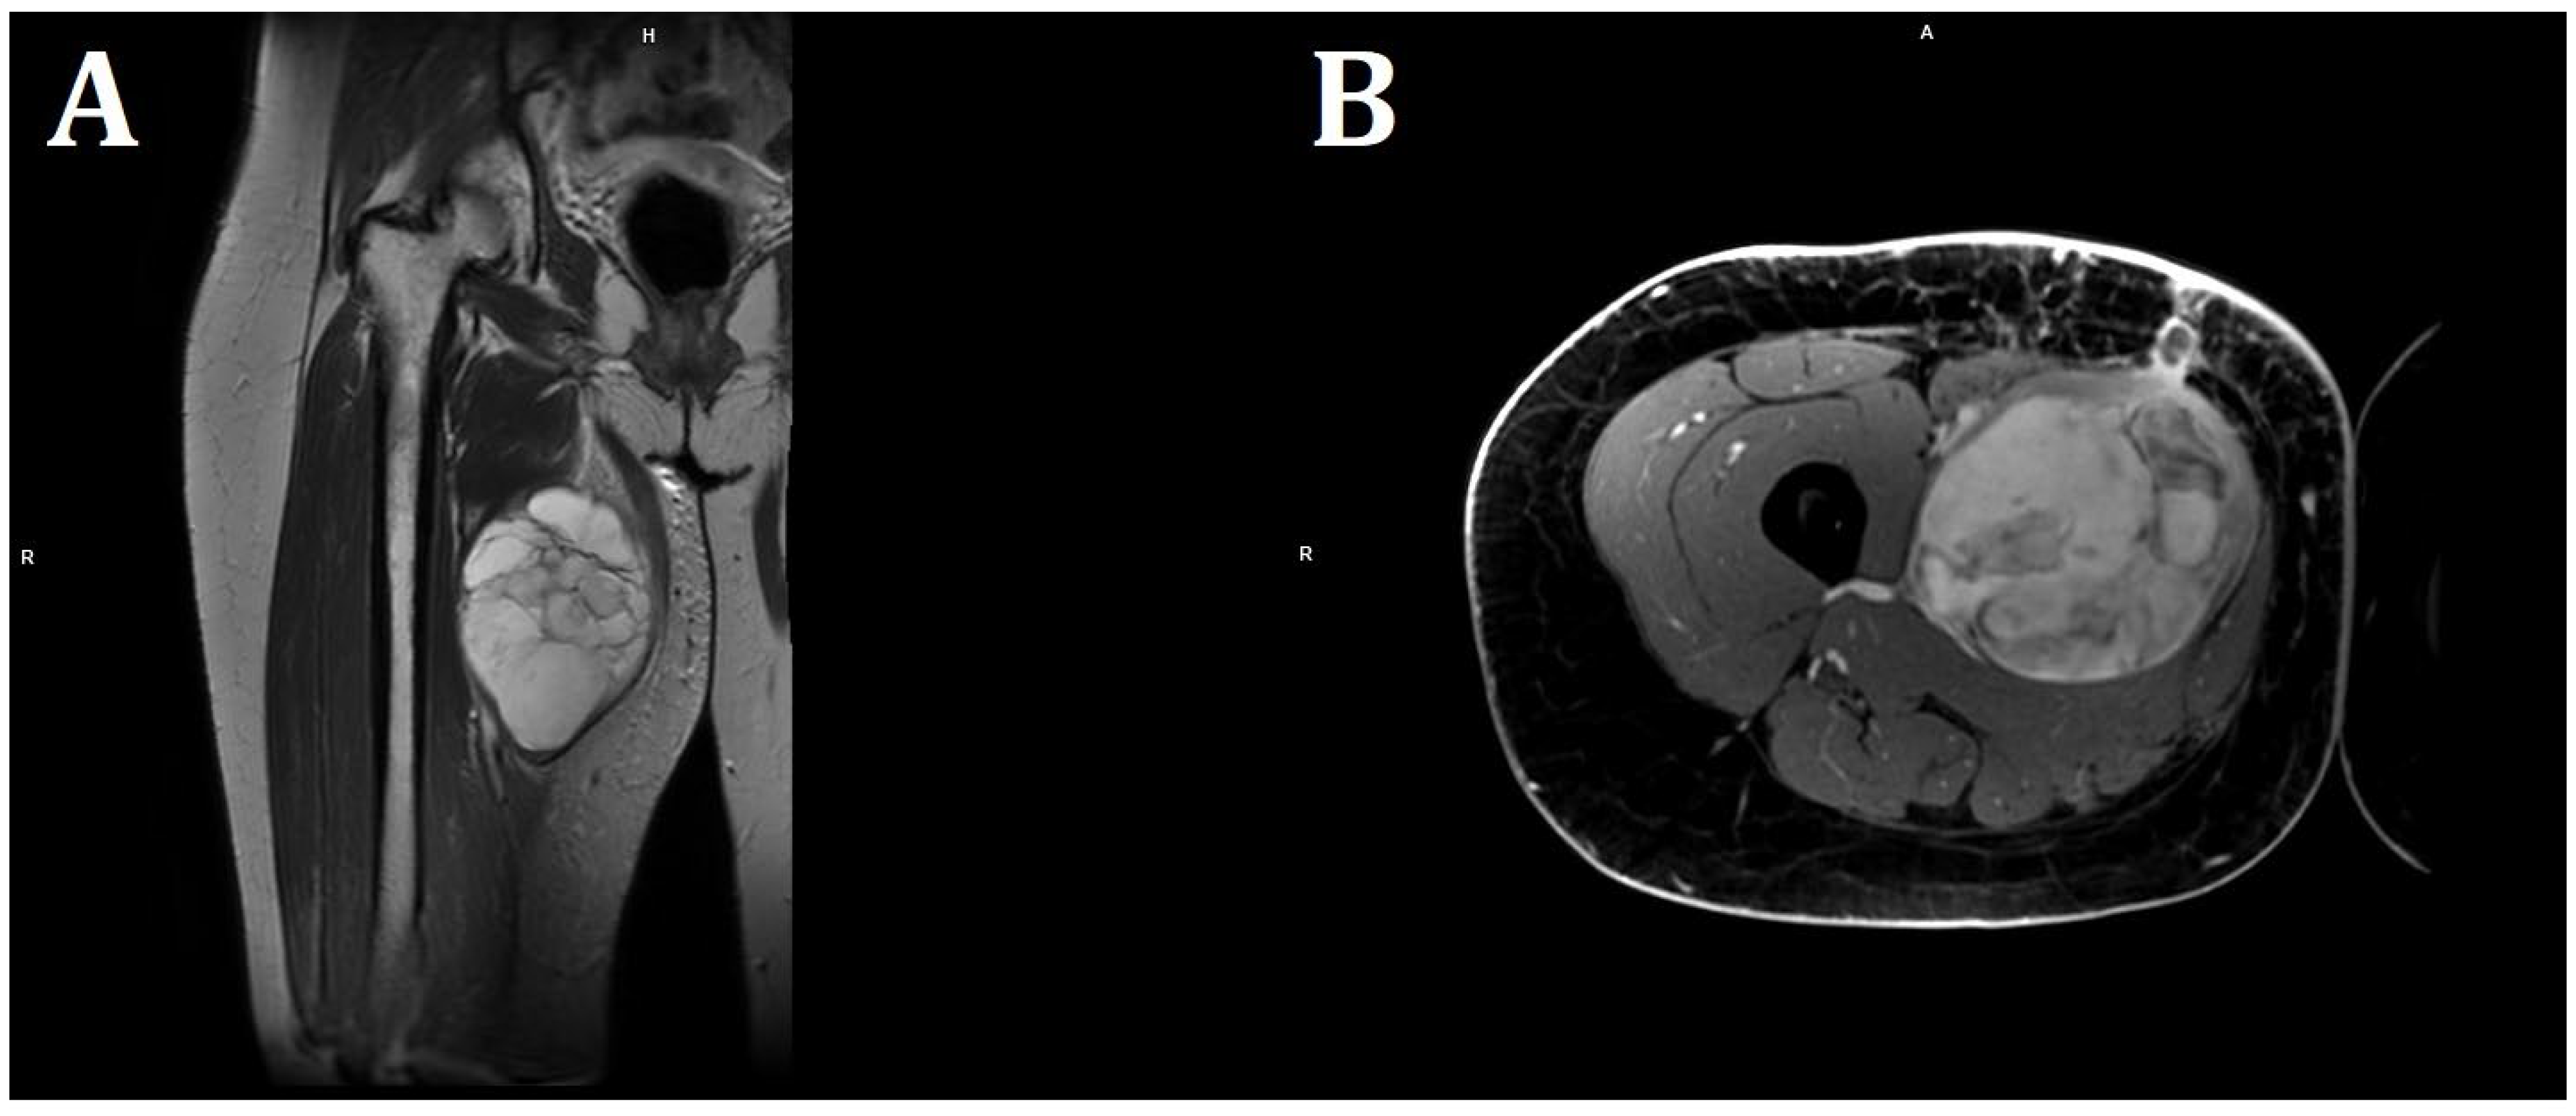

On the following day, computed tomography of the lower limb was performed. In almost the entire adductor muscle of the right thigh (the proximal part of the thigh, in the long adductor muscle), a large, well-demarcated, heterogeneous area measuring 96 × 86 × 175 mm (RL × AP × CC) was visible, showing a density of −5–22 H.U. in the native phase, with areas undergoing heterogeneous post-contrast enhancement up to 70 H.U. in the venous phase and 100 H.U. in the delayed phase. The image suggested a hematoma, and contrast enhancement in subsequent examination phases suggested active bleeding without a bleeding site detectable in a CT scan (Figure 2). For this reason, the patient was transferred to the Clinic of General and Vascular Surgery for surgical treatment and to manage the suspected bleeding.

Figure 2.

Picture of the tumor’s location and axial/coronal computed tomography imaging of a massive right thigh tumor—red circle (SOMATOM Edge Plus 128-layer CT scanner).

In the CT scan large, well-demarcated tumor density was −5–22 H.U. in the native phase, with areas undergoing heterogeneous post-contrast enhancement up to 70 H.U. in the venous phase and 100 H.U. in the delayed phase. Retrospectively, it is possible to consider a tumor with a lipid component when H.U. is less than 0 [14]. On the other hand, Hassan et al. suggested that most hematomas (64%) had mixed density with hyperdense components [19], and fat components typically have between −65 and −120 H.U. [20] Perhaps this was the reason why two specialists in radiology and diagnostic imaging suggested, based on this description and the images, that it could be a hematoma.